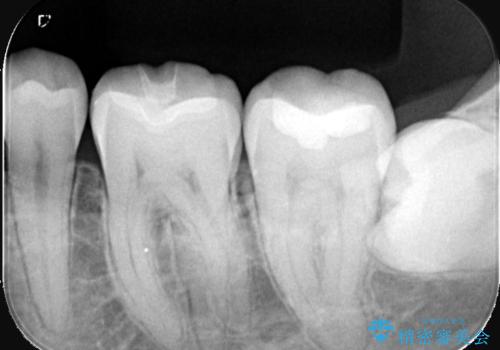

充填されているプラスチックの材料を除去したところ、う蝕が広がっていたため除去しCR裏層の後セラミックインレー修復をしています。セラミックインレーセット時は、ラバーダム防湿を行っています。